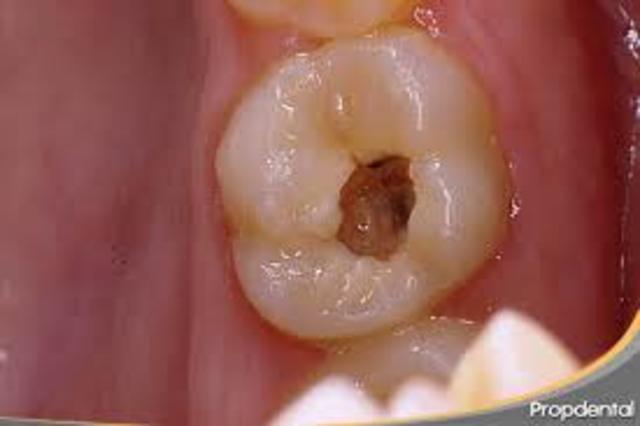

La caries dental ha sido descrita como una enfermedad multifactorial relacionada con la dieta, bacterias intraorales, composición de la saliva y otros factores.

Así la caries dental involucra la interacción en el tiempo de una superficie dental susceptible, las bacterias cariogénicas, y la disponibilidad de una fuente de carbohidratos fermentables, especialmente sacarosa.

Cuando la caries dental alcanza los tejidos dentarios profundos se convierte en una urgencia en los servicios estomatológicos, pero solo si se conoce cómo se inicia y se propaga esta afección, podremos curarla y prevenirla. Es en esta dirección hacia donde deben encaminarse los mayores esfuerzos que tiendan al control de la más frecuente de las enfermedades. Es por estas razones que nos vimos motivados a la realización de este trabajo.

El inicio del proceso carioso no se puede atribuir a una sola causa, debido a que para su desarrollo, se requiere de la confluencia de factores que determinan la lesión cariosa, es decir, que la agresión del esmalte dental sea de gran magnitud, que la resistencia del esmalte a la disolución ácida sea insuficiente, y que los mecanismos de remineralización del esmalte no tengan lugar (Dechaume M, Grellet M, Laudenbach P, Payen J. Estomatología. La Habana; 1985. pp. 5-7. Edición Revolucionaria).